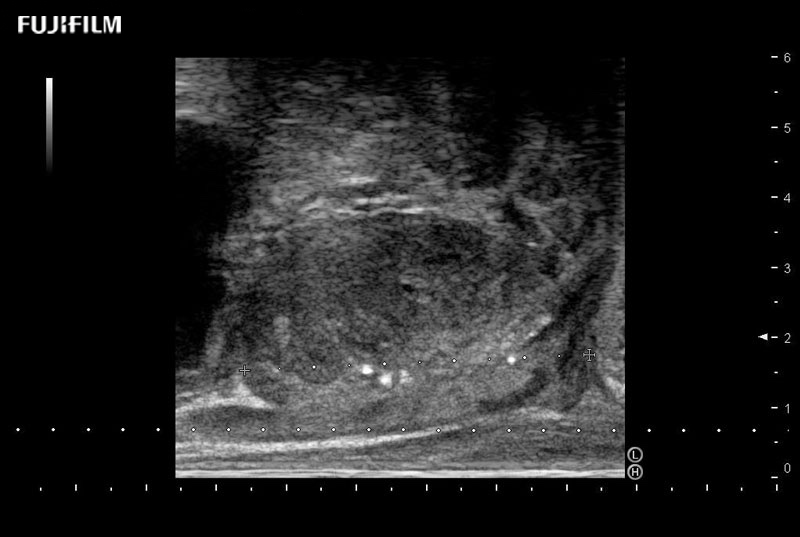

Abdominal transducer for biopsy, bladder and renal applications.